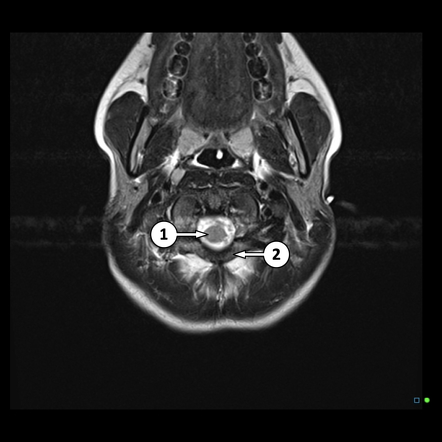

。persp_2_5_35fig5.jpg。